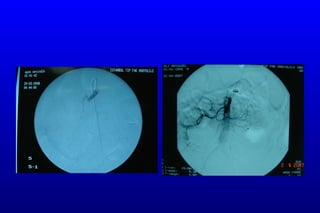

Hastaya  anjiografi yapıldı. SMA total oklüde / çölyak trunkusta %90-95 darlık saptandı. Çölyak trunkustaki darlığa stent uygulandı.

Süperior mezenterik arter Çölyak trunkus

Çölyak trunkusa stent sonrası

tPA öncesi tPA sonrası

KLİNİK 15/03/2009 :Hastaacil cerrahi kliniğine kabul edildi. Yapılan tetkiklerinde SMA distalinde parsiyel trombüs saptanması üzerine diagnostik laparoskopi yapıldı. Low flow state saptandı. Ameliyat sonrası anjiografi yapılarak tPA uygulandı. İşlem sonrası yoğun bakıma alınan hastanın sorunu olmadı. 16/03/2009 :Hastaya kontrol anjiografi yapıldı parsiyel trombüs görüntüsü devam ediyor. Hastaya tedavi dozunda DMAH başlandı.